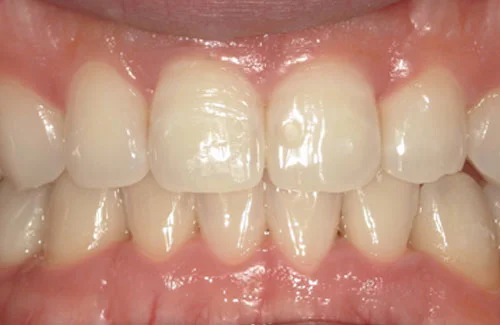

<症例7>歯がガタガタで噛み合わせが悪くお悩み

抜歯無し・マウスピースのみで矯正した症例です。

もともと歯列弓が非常に狭く、V字に近い形をしていたので噛み合わせも非常に不安定でした。

また、下顎前歯部がかなり上の方に生えていたため、下の前歯が上の前歯を突き上げてしまい出っ歯の状態になっていました。

現在では見た目はもちろん、臼歯の噛み合わせも改善しております。

奥歯の患者様も大喜びでした。

患者様と症状

主訴:歯のガタガタ、噛み合わせが悪い

性別・年齢:20代女性

問題点:叢生(重度)、V字歯列弓、ディープバイト

診断:前歯部の叢生を伴うアングルⅠ級、骨格性Ⅰ級の不正咬合

主なリスク:臼歯の移動に伴い一時的に咬合しにくくなる、歯肉退縮

症状:叢生(そうせい) 過蓋咬合(かがいこうごう)

治療内容

治療期間:1年10ヶ月

治療費用:990,000円(税込)

プラン:Full2プラン

抜歯:無し

再診治療費:無し

追加治療費:無し

保定装置費:無し

治療前後の写真